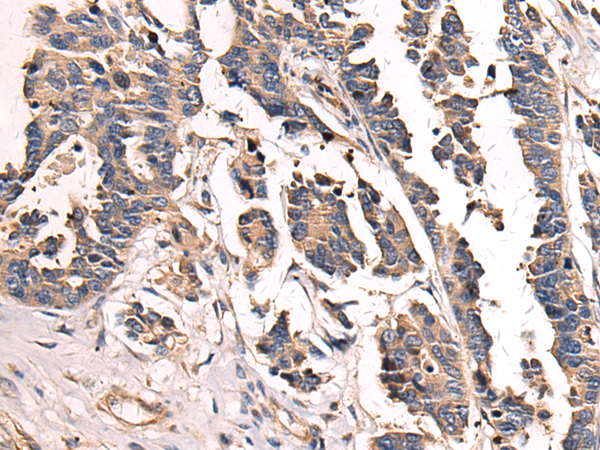

The image is immunohistochemistry of paraffin-embedded Human colorectal cancer tissue using (SH3BGR Antibody) at dilution 1/70. (Original magnification: ×200)